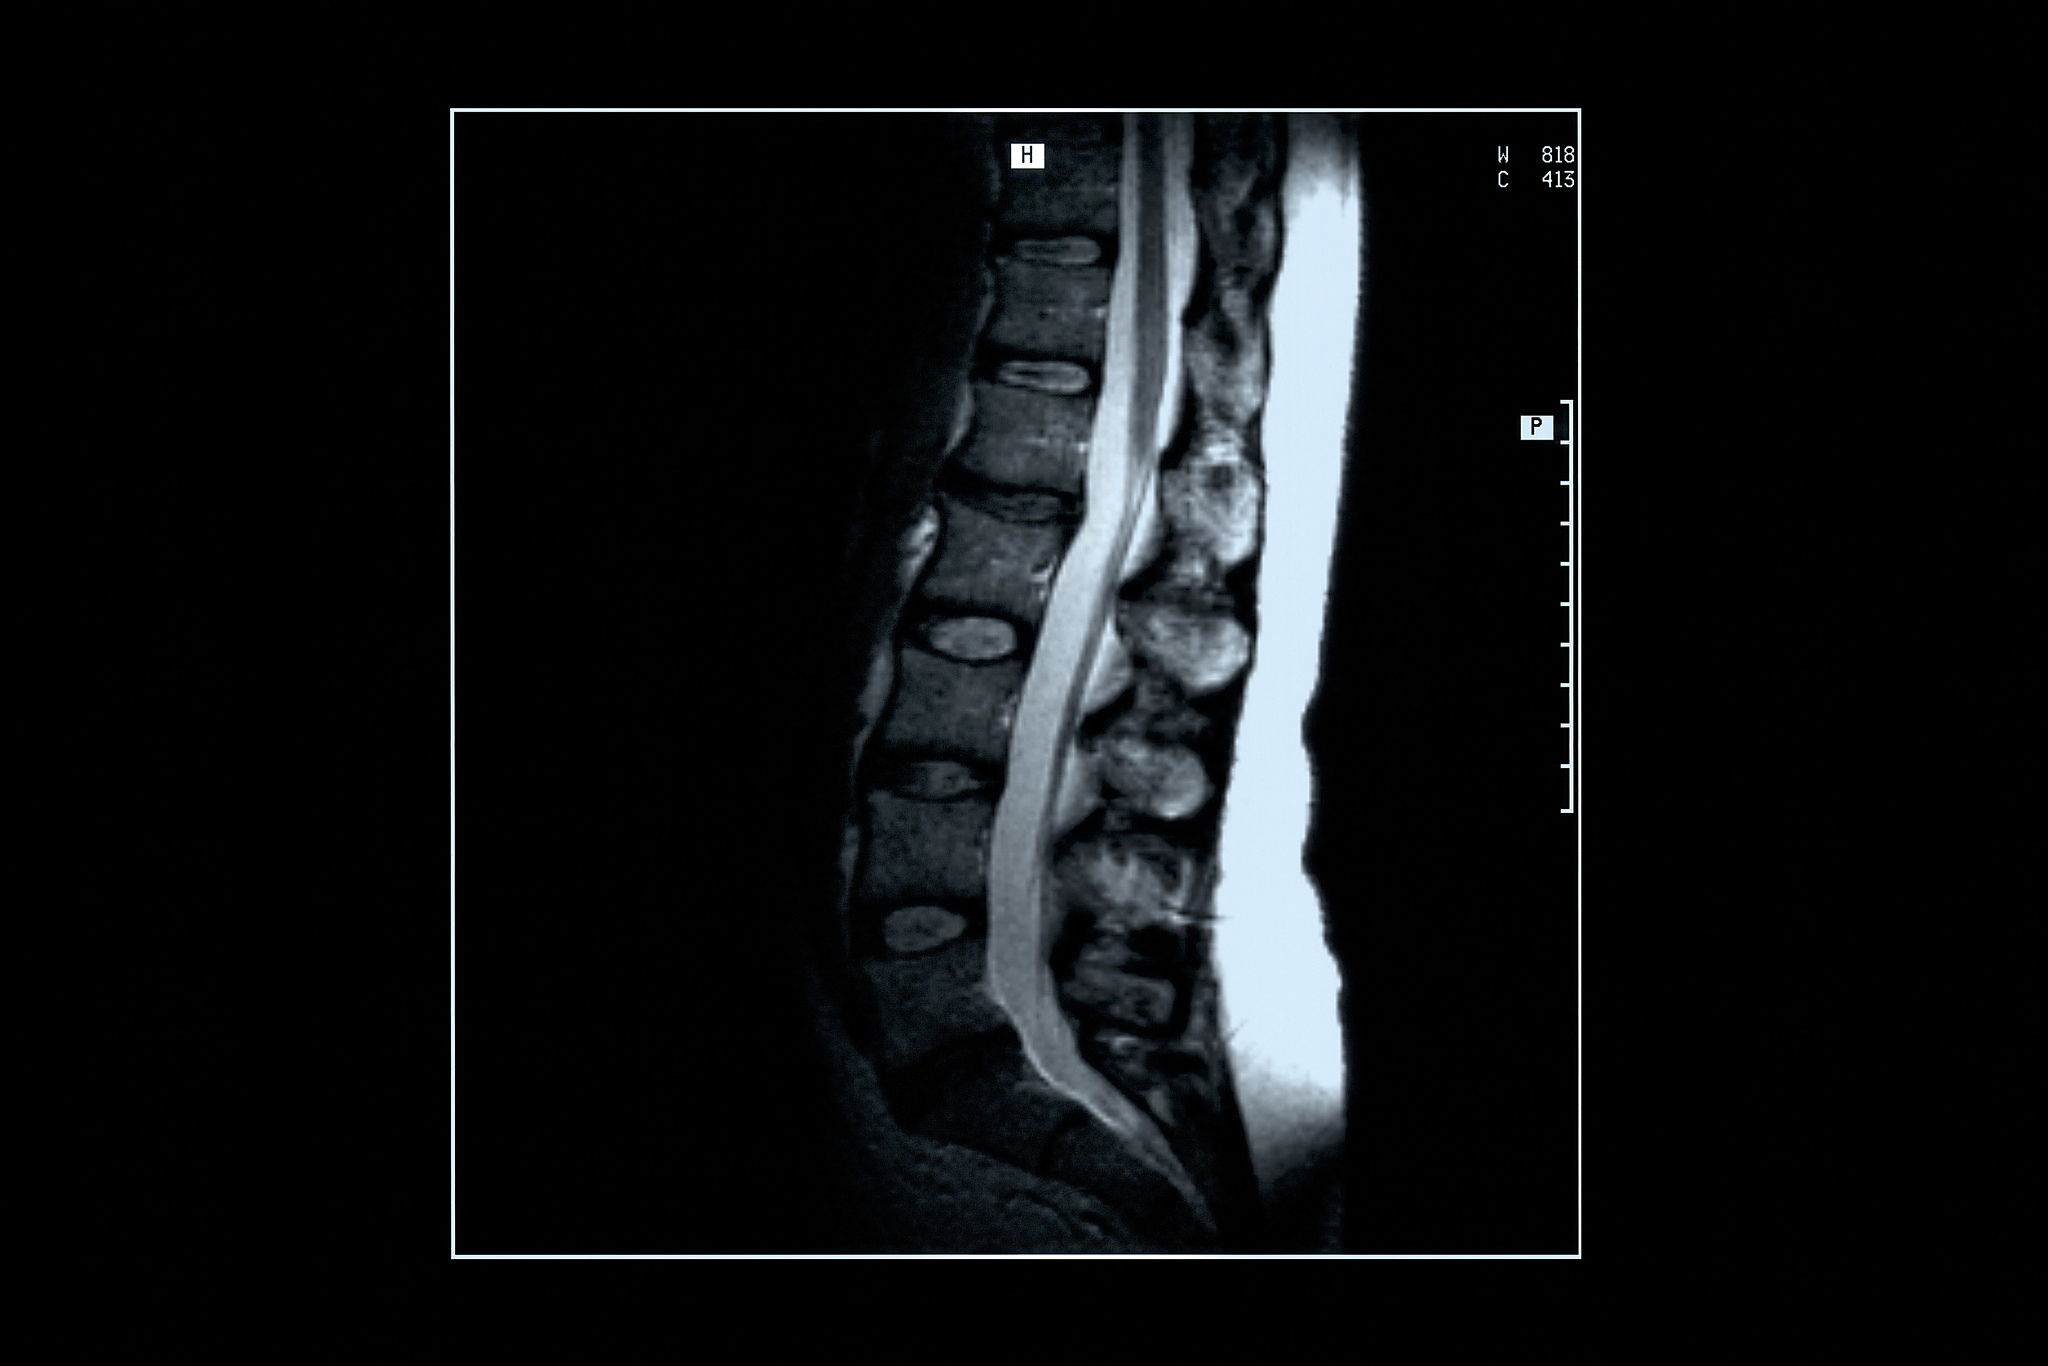

椎体成形术(PVP)是一种微创手术,用于治疗椎体压缩性骨折。然而,并非所有患者都适合进行PVP。以下是一些常见的相对禁忌症:

2. 严重的椎体坍塌: 如果患者的椎体坍塌非常严重,PVP可能无法有效地恢复椎体的形态和稳定性。

3. 椎间盘破裂: 如果患者的椎间盘已经破裂,PVP可能无法有效地修复椎间盘的损伤。

5. 严重的神经系统疾病: 患有严重的神经系统疾病的患者进行PVP可能会增加神经系统并发症的风险。